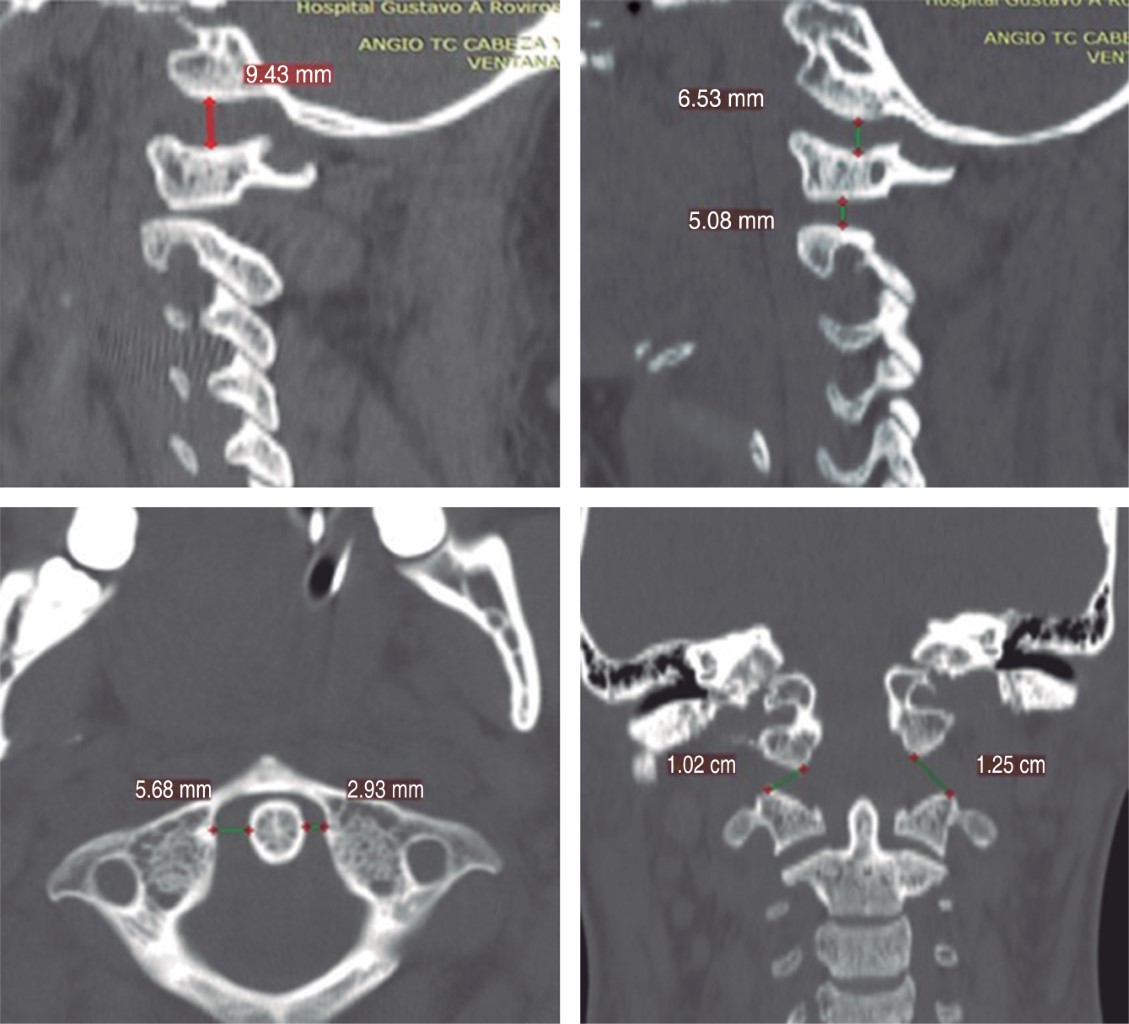

Introduction: injuries to the craniocervical junction with instability secondary to trauma are rare; with complications with a high mortality rate. When both lesions are present; the patient's prognosis for survival and recovery is usually very poor. Surgical treatment for reconstruction of the occipitocervical junction are complex and uncommon procedures; in most cases they have been studied in the treatment of degenerative and rheumatic pathologies. Clinical case: 27-year-old female patient, with combined occipitoatloid-atlantoaxial instability secondary to an accident in a motorcycle-type vehicle; which has multiple injuries. Diagnosis: clinic with neurological deficit; radiological studies of trauma, and axial tomography of the skull and spine, where data of instability at the C0-C1 and C1-C2 levels are evident. Interventions: multidisciplinary management and subsequently occipitocervical reduction and fixation with Harms technique of the injuries due to traumatic vertebral instability; C0-C1, C1-C2 and C2-C3. Follow-up: 9 months after the intervention, with adequate clinical evolution. Conclusions: although there are few publications and guides on the diagnosis, ideal moment of intervention and optimal stabilization method in cases of instability due to trauma, we recommend a multidisciplinary approach. Early diagnosis and treatment directly influence the final prognosis and quality of life of these patients.

Figure 1